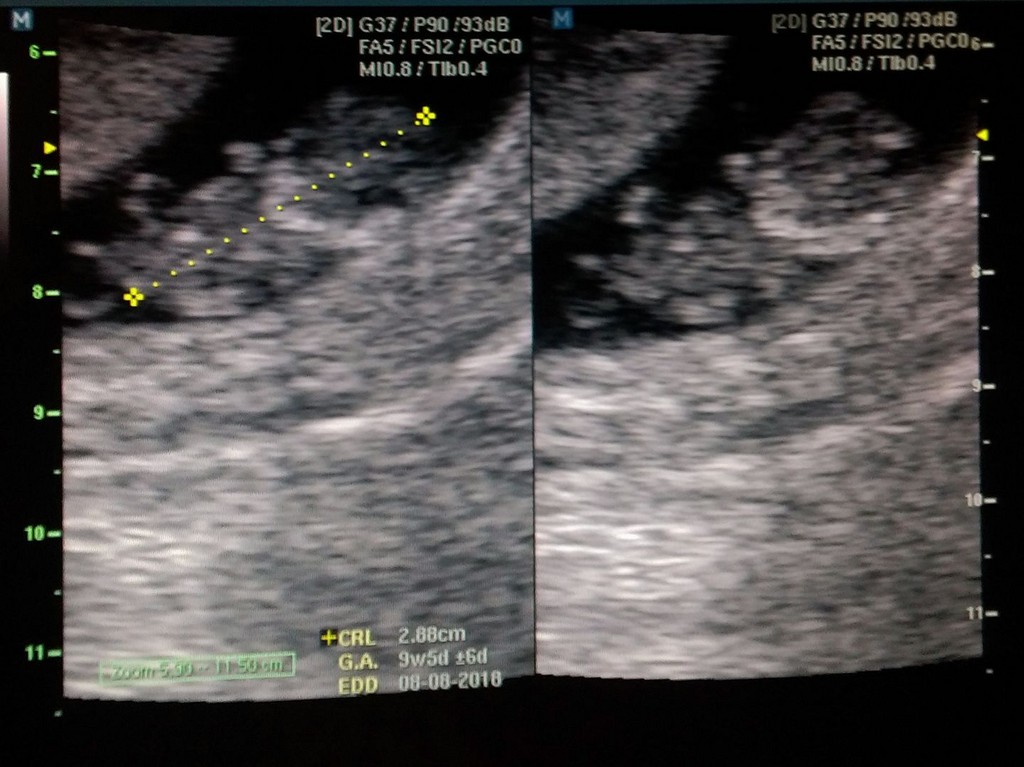

▲楊雅晴宣布懷第二胎。(圖/翻攝自臉書「百吻巴黎Kiss.Paris-楊雅晴」)

曾經出版《百吻巴黎》的楊雅晴在去年初結婚並生下愛女「咪哈」,臉書上時常可以看到她和寶貝女兒的可愛互動,她在16日晚間貼出一張寶寶的超音波照片,開心宣布懷了第二的孩子,而且明明就有做避孕措施,但二寶還是照常報到,讓她大嘆根本「神嬰」。

楊雅晴在臉書專頁「百吻巴黎Kiss.Paris」PO出這張超音波照片,表示大女兒咪哈準備要當姊姊了,「這是閃過保險套百分之九十幾的網羅的神嬰」,看來這個二寶也是狠角色,不管如何阻擋都硬要來。而她的愛女咪哈在幾天前剛剛滿一歲,現在又準備要當姊姊了,好消息不斷。